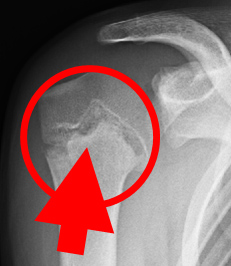

正常

(レントゲン)

リトルリーガーズ・ショルダー